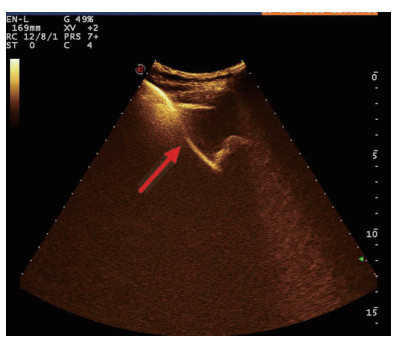

| 图 2 穿刺后经引流管超声造影,显示置管路径(箭头处) |

术后再次经肘静脉超声造影同时经引流管超声造影:PTGBD后,再次经肘静脉快速团注SonoVuel 2 mL,在造影成像模式下进行观察肝脏被膜、胆囊床穿刺路径有无造影剂外渗,腹腔内有无外渗凝聚的造影剂,判断有无活动性出血及出血程度,如判断出血速度快、出血量较大,考虑动脉性出血,及时改为开腹或腔镜手术止血。PTGBD术后经引流管超声造影,置管成功后快速抽出胆囊内残留胆汁,减轻胆囊压力后,在超声造影模式下直接经引流管注入配制待用的稀释声诺维造影剂20 mL,实时动态的观察造影剂在胆囊腔内的充盈范围(图 2、3),评估引流管的通畅程度及引流范围、观察其在胆囊腔内的位置走形及卷曲情况、观察胆囊周边及腹腔内有无造影剂外渗。如患者腹痛症状加剧,结合经引流管超声造影判断有胆汁漏出表现,应持续监测观察患者生命体征及保守治疗效果,必要时及时改行开腹或腔镜手术治疗。

超声造影是利用超声造影剂微泡(本组应用的是声诺维超声造影剂微泡)在低机械指数声波照射下发生共振,产生线性及非线性谐波回声信号,形成造影增强图像的技术,是近年来新兴的超声技术,具有实时、可连续观察、无辐射、可重复性好、毒不良反应少等优势,为临床提供了全新的诊疗手段[14]。经肘静脉注入的标准配置超声造影剂是一种血池造影剂,可以反映组织的血流灌注情况同时亦被广泛应用于肝、脾、肾等实质性脏器破裂的诊断,其诊断的敏感性及特异性均明显优于二维超声,且与增强CT有较好的一致性[15-16]。本组病例术前经肘静脉注入标准配置造影剂后,胆囊壁均显影增强,胆囊穿孔及周边积液处表现为造影无充盈区,穿刺置管后再次静脉路超声造影,迅速发现术后出血部位且可敏感评估是否为活动性出血(经手术证实)。除1例因活动性出血中转腹腔镜手术外,其余32例置管成功后经引流管口注入稀释造影剂20 mL(1:200稀释),评价引流管位置、引流范围及是否出现胆汁外漏取得良好效果,所有引流导管均能够清晰显示引流导管置入路径、引流管形态及引流范围,引流管置入恰当者,头端位于胆囊内,全管显影清晰,造影剂弥散区域与胆囊大小吻合; 置管后胆汁漏出者,可见造影剂沿引流管周边渗出[17-18],本组中3例出现造影剂外渗,其中两例渗出范围局限于胆囊床附近,未渗出至游离腹腔,患者腹痛症状稍有加剧,经胆囊减压及对症处理后好转,其中1例见造影剂渗出至肝肾间隙,患者腹痛症状加剧明显,考虑置管位置不当,余行急诊腹腔镜手术治疗,术中证实为系膜胆囊,且可见引流管侧孔部分外露。笔者的经验是,术前选择静脉路超声造影有助于对胆囊情况的评估及穿刺点的选择,术中正确选择穿刺针的入路有利于提高穿刺引流的成功率。首先是胆囊穿刺部位的选择应选择在靠近胆囊颈侧,此处胆囊位置比较固定,受体位影响较小,且胆囊床结缔组织较为固定,有助于将漏出胆汁包裹局限,其次是进针方向与胆囊床尽可能保持垂直,减少进针位置的偏移,同时置管成功后应即刻尽量抽尽胆囊内的感染性胆汁,生理盐水冲洗后行经引流管稀释超声造影有助于判断置管位置、引流范围及是否出现胆汁漏出,减少不必要的并发症发生率。穿刺引流后可以根据患者的营养状况待窦道形成稳定后择期拔除引流导管。对全身情况改善适合手术治疗且有手术意愿者可以考虑择期胆囊切除术。